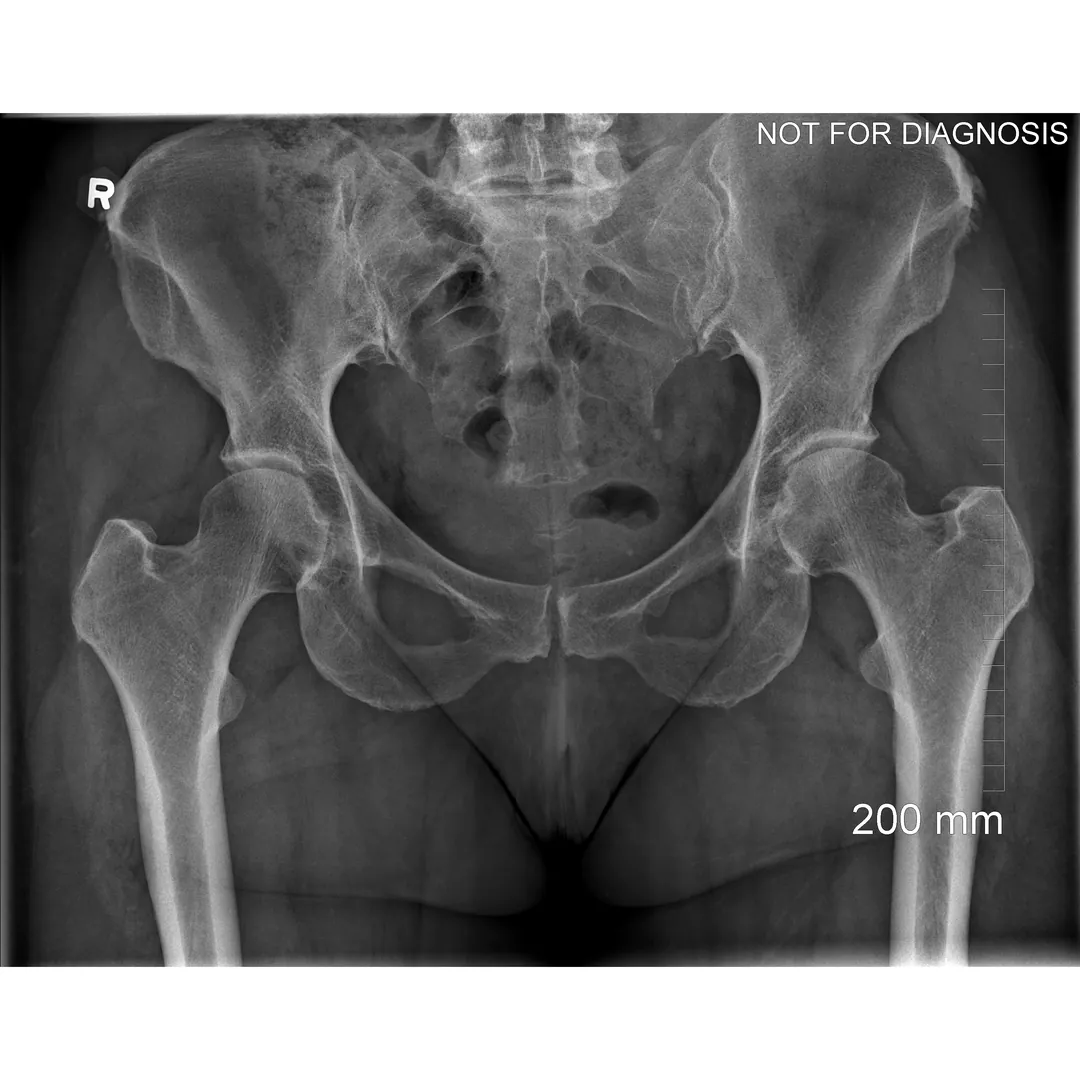

A total hip replacement (also called total hip arthroplasty) is a surgical procedure in which a damaged or worn hip joint is replaced with artificial components. The hip is a ball-and-socket joint, meaning the ball at the top of the thigh bone sits in a socket on the pelvis. During surgery, the damaged ball (femoral head) is replaced with a metal or ceramic ball attached to a stem, and the damaged socket is replaced with a metal cup lined with plastic, ceramic, or metal.

Hip damage caused by conditions such as:

- Osteoarthritis (most common)

- Rheumatoid arthritis

- Avascular necrosis (loss of blood supply to the hip bone)

- Hip fracture or trauma

- Congenital or developmental hip disorders

- The surgeon removes the damaged bone and cartilage and inserts the artificial joint